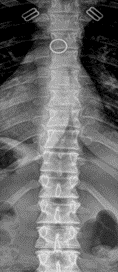

Radiographic examination of the thoracic spine was normal with no osseous abnormalities noted (Figure 1 and 2). The lumbar spine radiographic study revealed several unexpected findings.